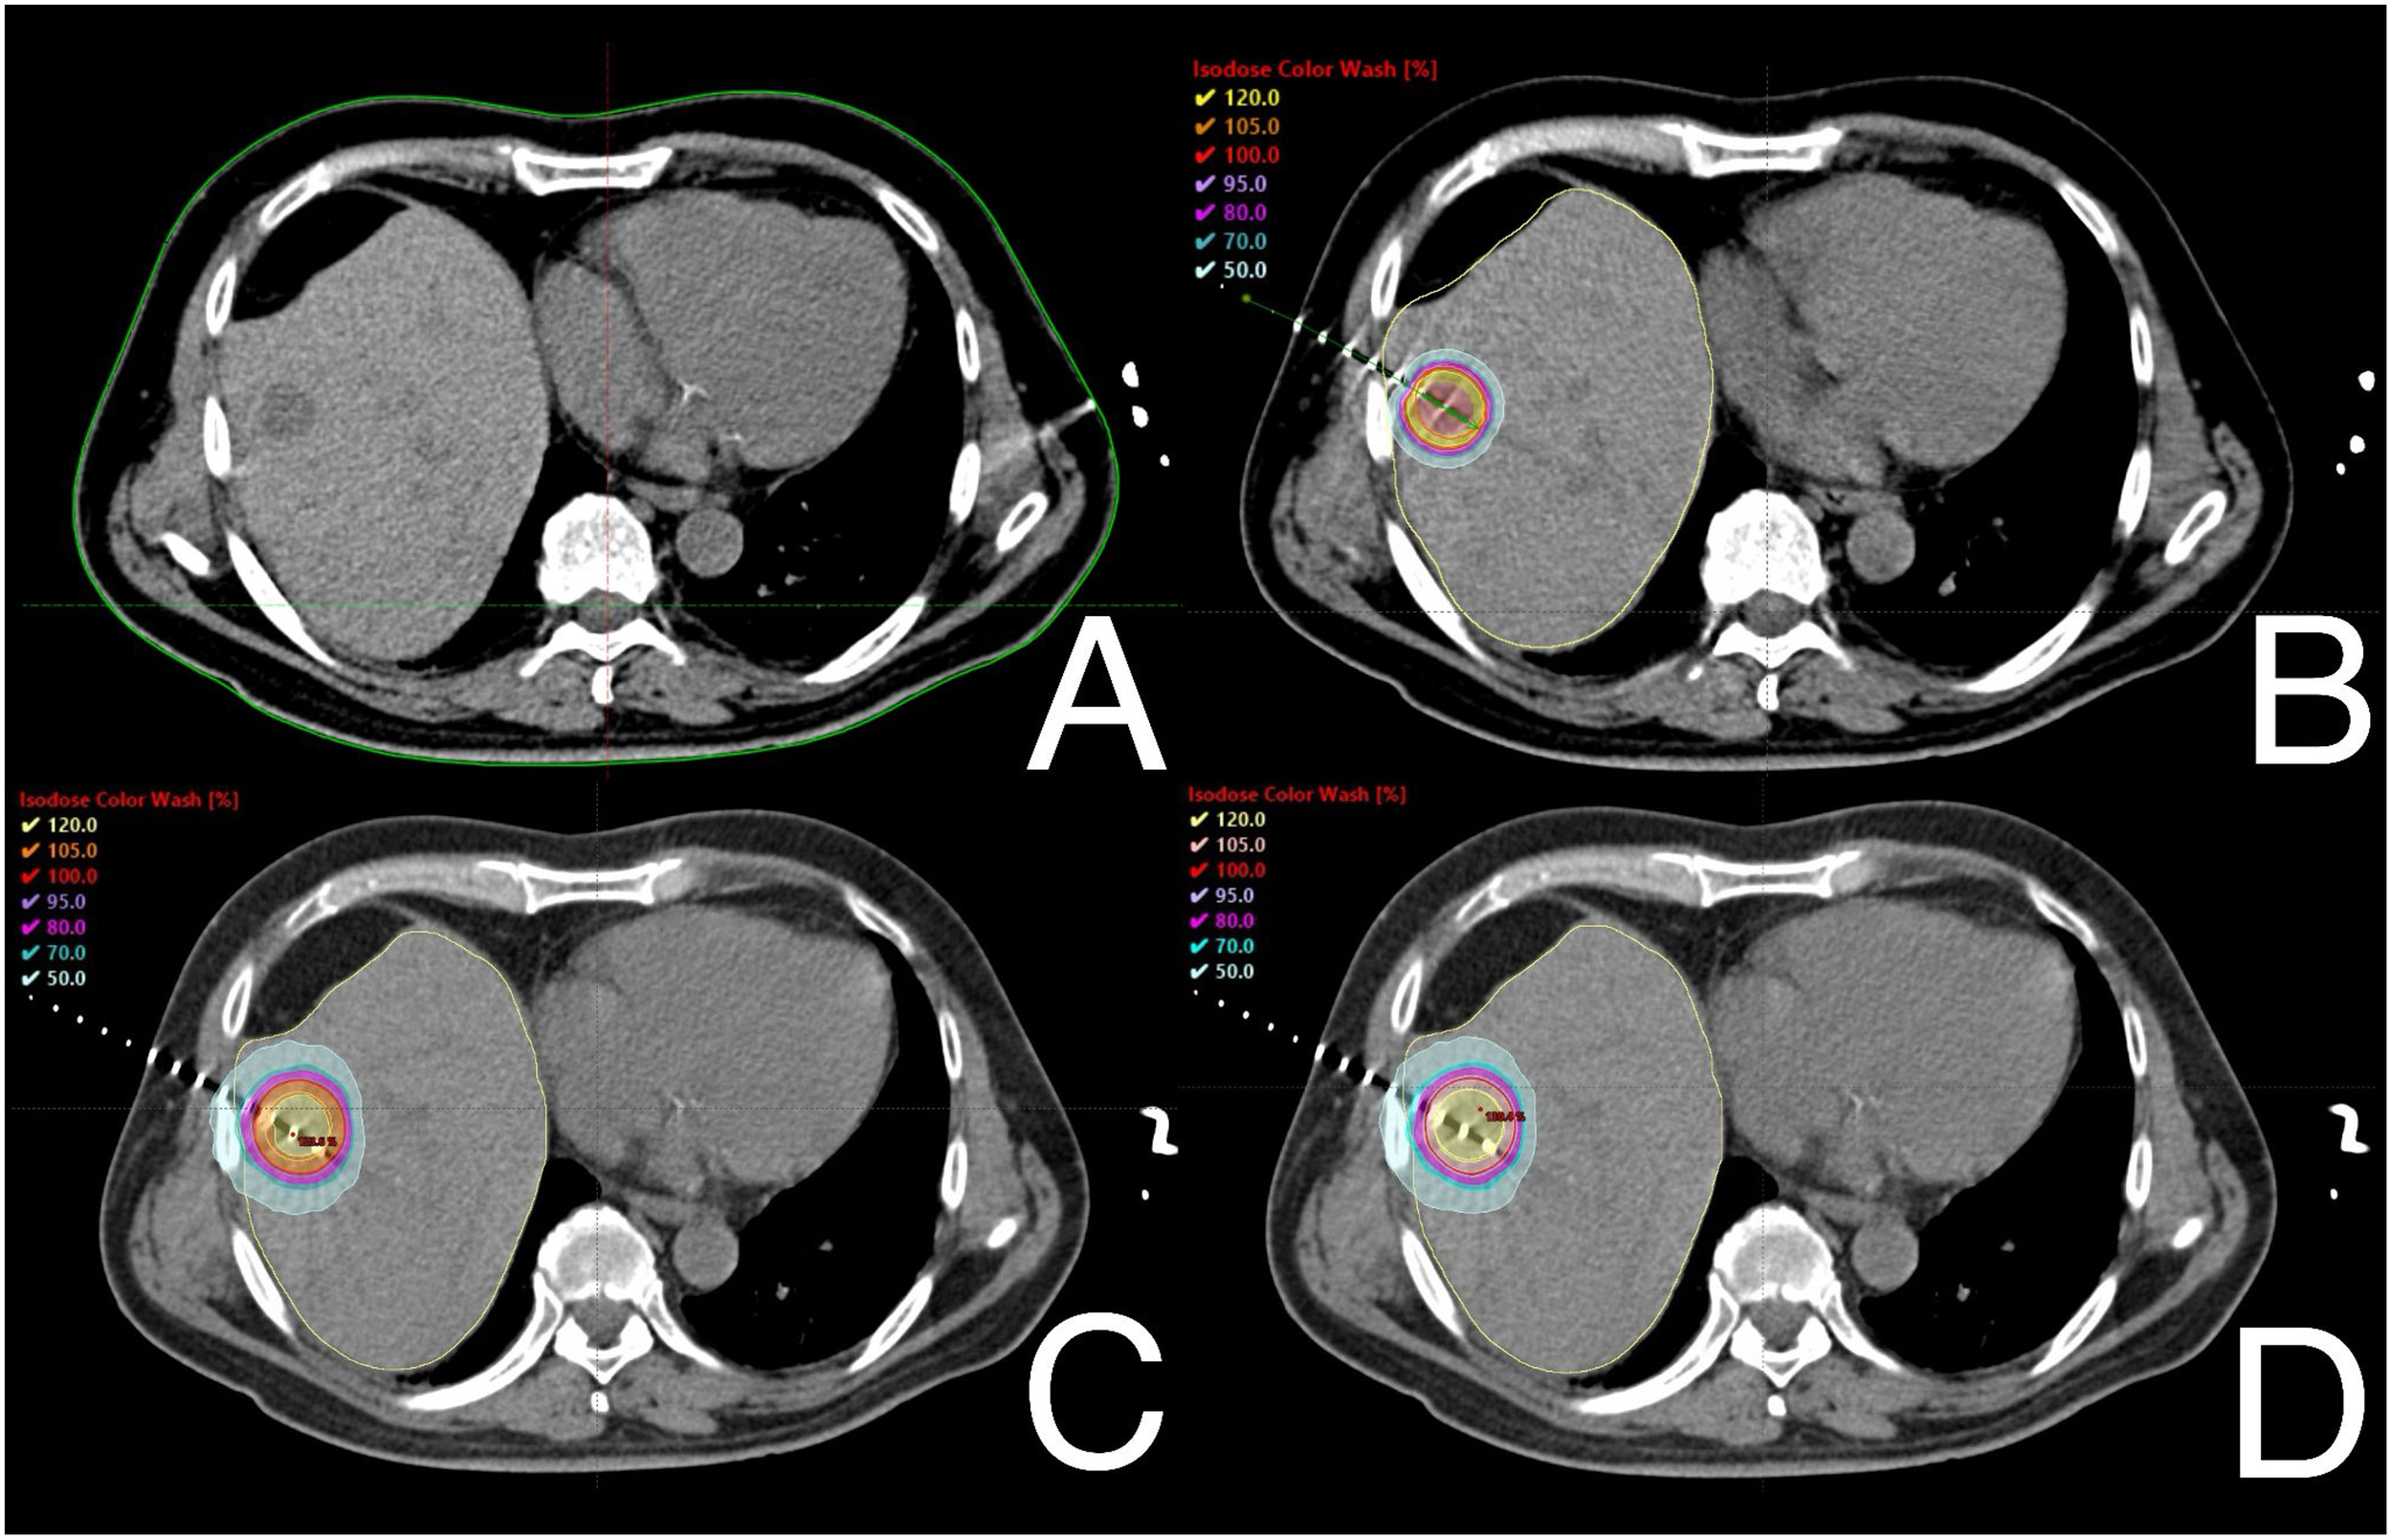

PTVs dose coverage: a crucial analysis

The statistical analysis revealed significant differences in certain dosimetric variables for PTVs. Plans developed for CT-BRT showed significantly better median D50, D90, and Dmean values. However, there were no differences in the Dmean and D50 parameters between both SBRT modalities. SBRT plans also demonstrated superior results in terms of D98 and V23.75Gy compared to those prepared for CT-BRT. There were no significant differences related to V25Gy between SBRTtb and CT-BRT. On the other hand, SBRTtb plans exhibited better D98, V23.75Gy, and V25 values compared to those prepared for SBRTh and CT-BRT. Figure 1 illustrates the dose distribution within PTVs for a selected liver metastasis. A detailed overview of the dose distribution within PTVs across the selected techniques is provided in Supplementary Material Table S1.

Figure 1

Example of dose distribution profiles within PTVs of one of selected patients with metastasis in fifth liver segment: diagnostic scan taken before treatment (A), CT-BRT (B), SBRTtb (C) and SBRTh (D).